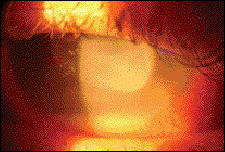

Similar to SAC and PAC, VKC produces bulbar and palpebral conjunctival signs, however, those associated with VKC are typically more severe than the other sub categories. When coagulated exudate adheres to the inflamed palpebral conjunctiva, a pseudomembrane is formed. These membranes loosely adhere to the conjunctiva and can be removed by peeling with forceps or a moist cotton swab. Along with allergic conjunctivitis, pseudo-membranes may be found in cases of epidemic keratoconjunctivitis (EKC), ligneous conjunctivitis and bacterial infections. In addition, corneal findings are common with VKC by way of a mechanism produced by the irregular superior conjunctiva eroding the conjunctiva. Corneal signs may range from punctate epithelial keratopathy to areas of corneal epithelial macroerosion and shield ulceration (see figure 3, above).